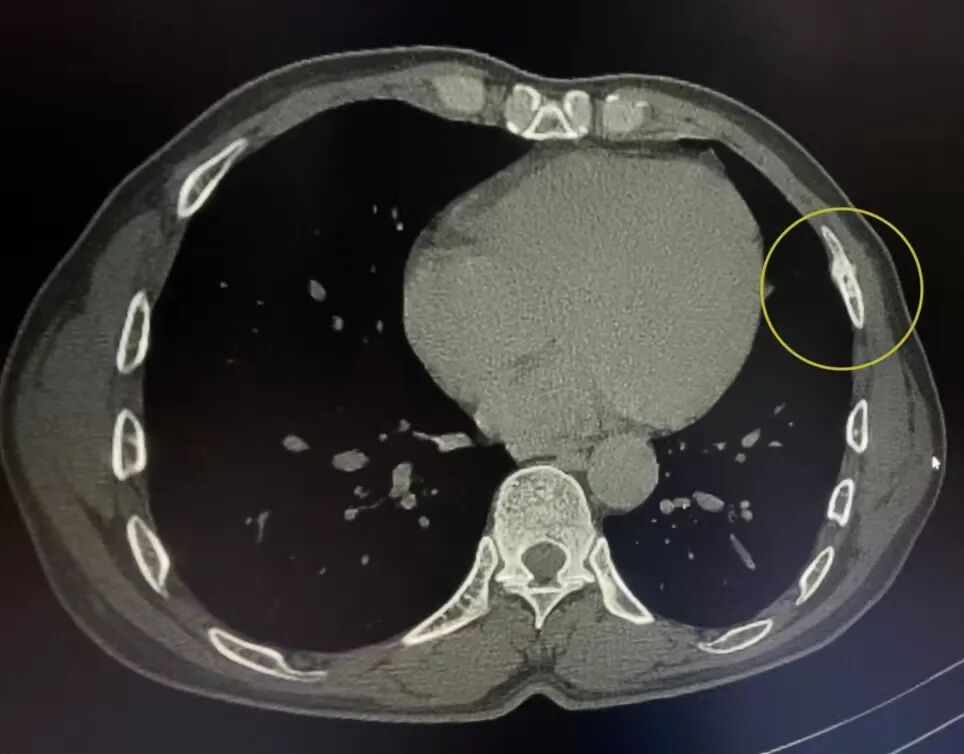

案例3、44岁的患者肋骨骨折复查平片未能明确显示骨折部位,CT扫描显示左侧第五前肋骨皮质不规则、边缘骨痂形成。